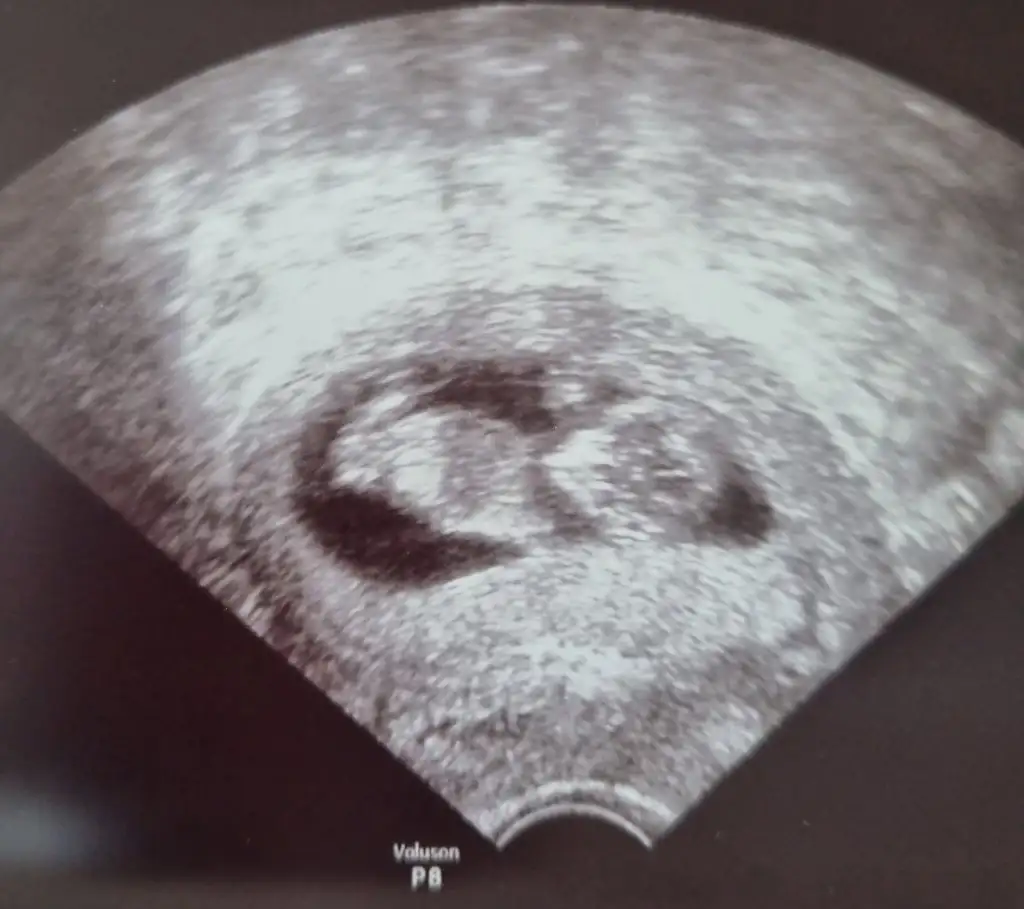

Net değil ama kız sanki başka USG varsa paylaşın 11 12 13 haftalar olmalıTahminlerinizi alabilirmiyim??? 12. Haftadan resim

Net değil ama kız sanki başka USG varsa paylaşın 11 12 13 haftalar olmalı

Yukari dogru cikanlar bacaklari degilmiNet değil ama kız sanki başka USG varsa paylaşın 11 12 13 haftalar olmalı

Ben size yazmıştım kız dedim diğer konudaBana ısrarla bakmadınız 12 hafta karından